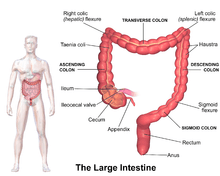

Illustration of the large intestine

Illustration of the large intestine Diagram of human gastrointestinal tract